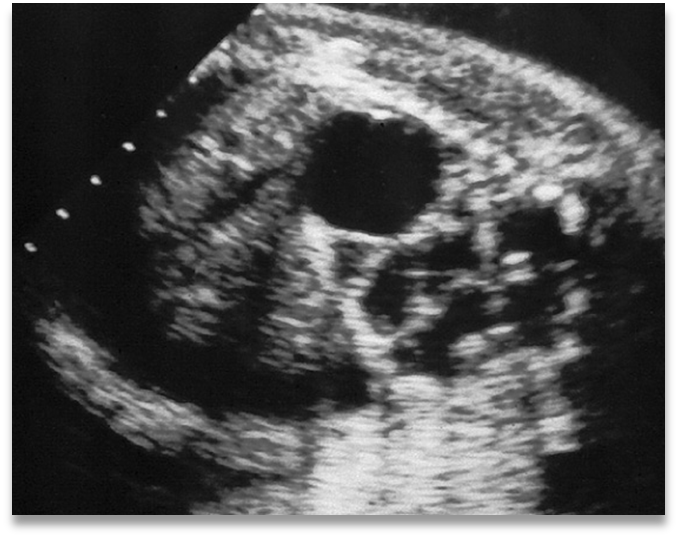

hydronephrosis